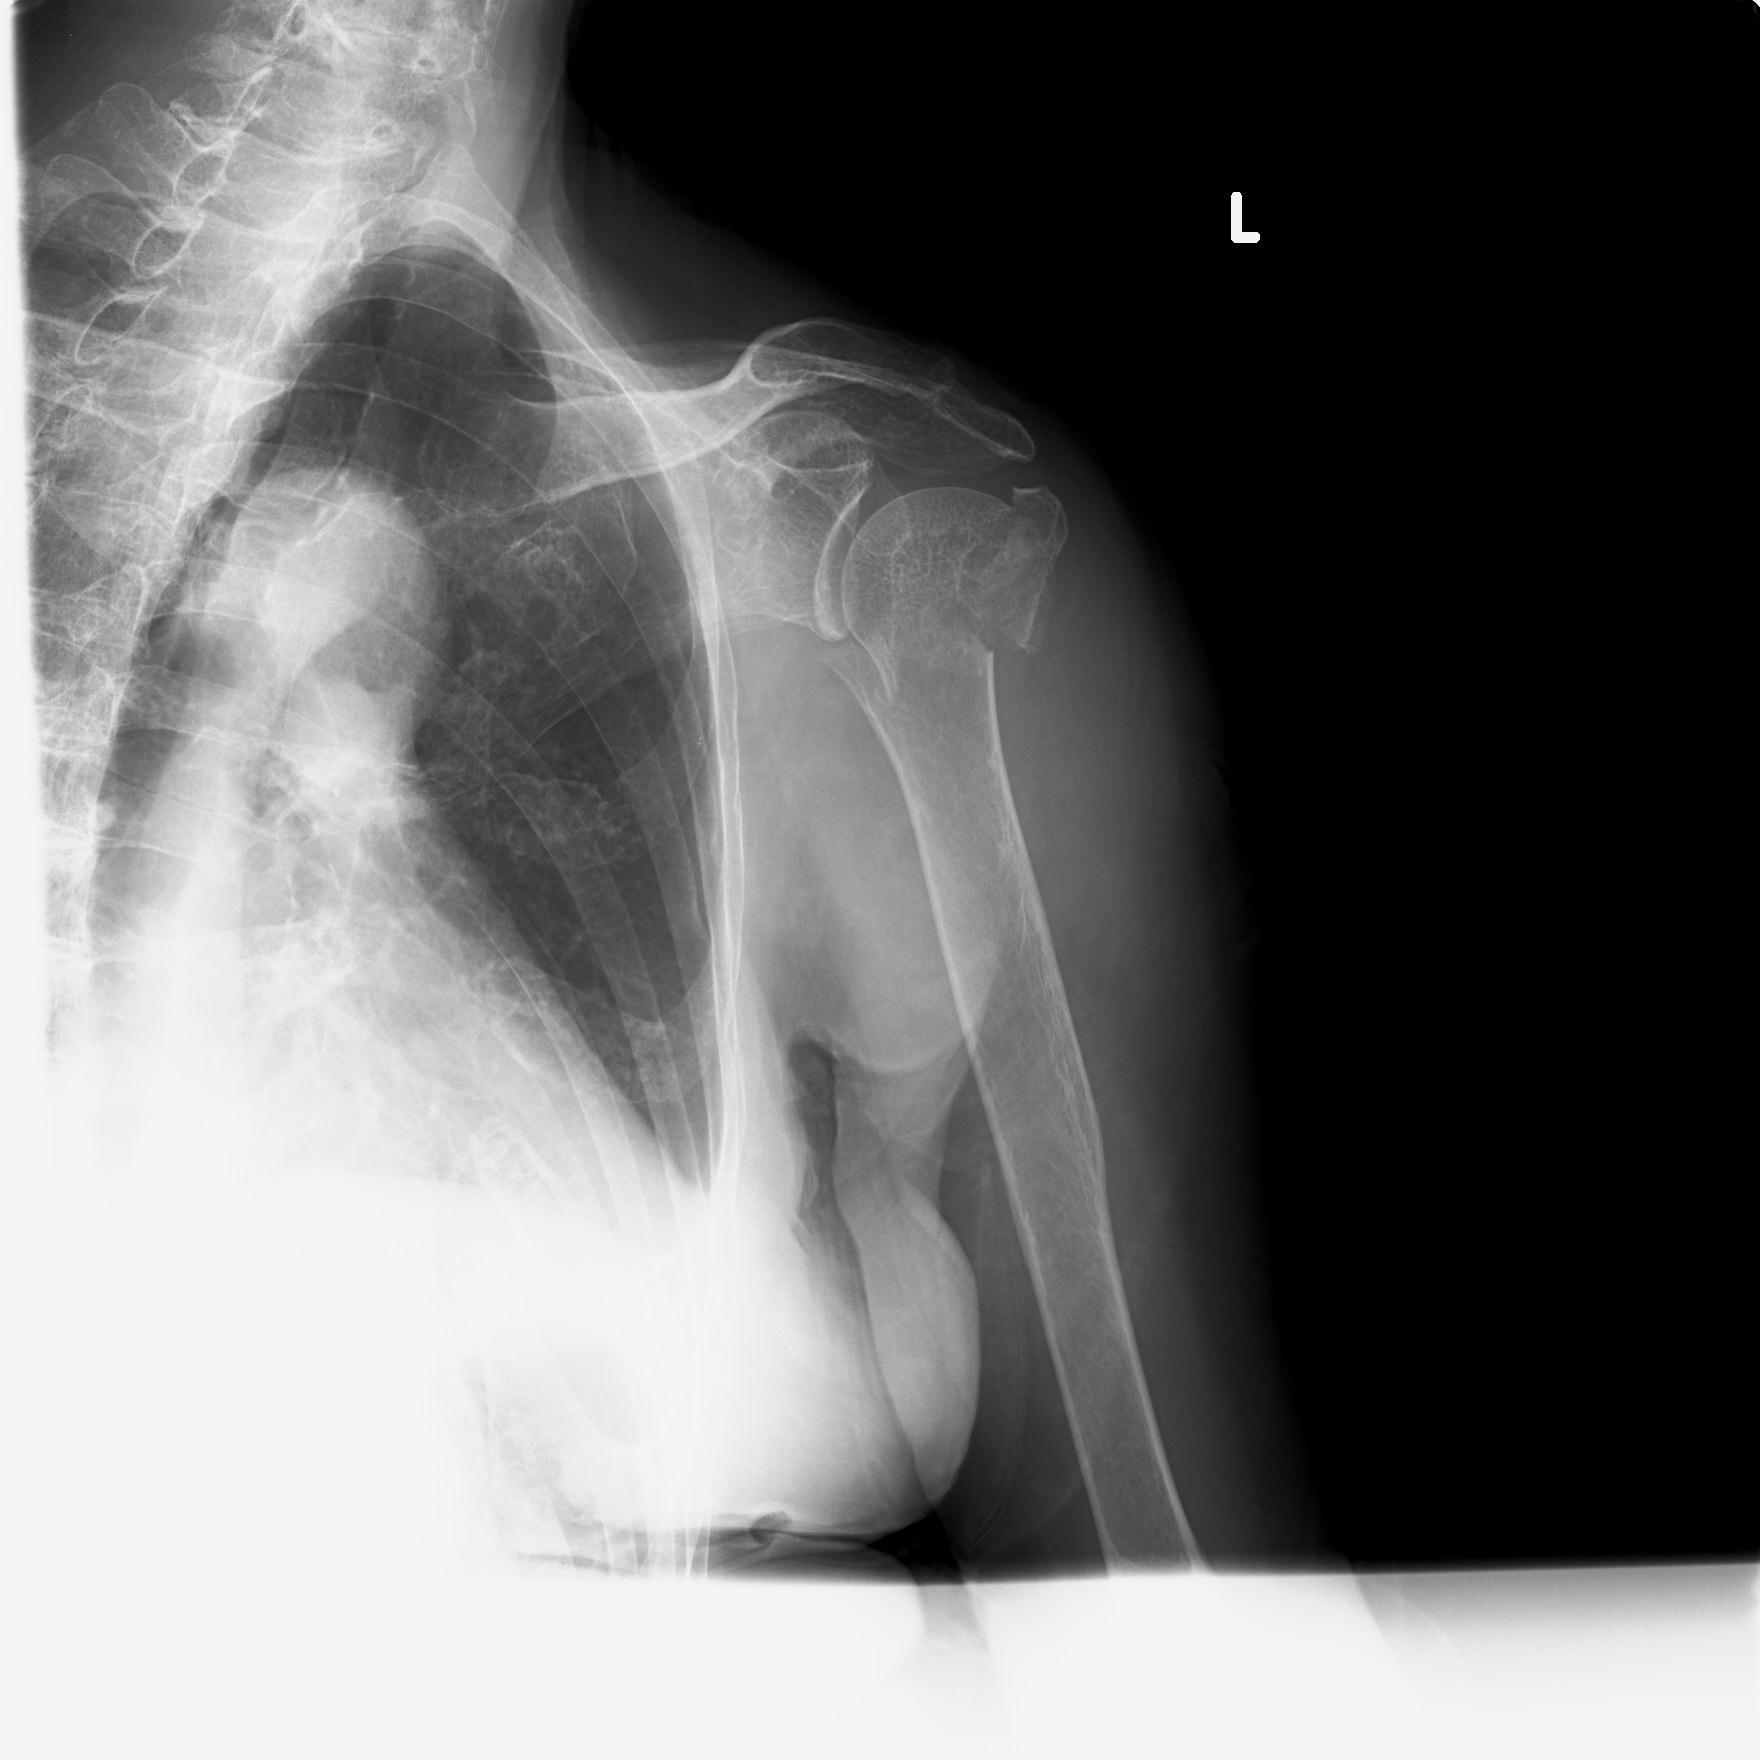

110214 12/20 肩 2R 12/21 肩 4R 72歳女性 左上腕外科頚プレート